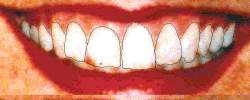

Detalhe ampliado da fotografia do indivíduo a ser

confrontado com a ossada. A investigação policial evidenciou fortes indícios de que a

ossada correspondia a este indivíduo. A identificação judicial tradicional

(dactiloscopia) ficou prejudicada em função da carbonização. |